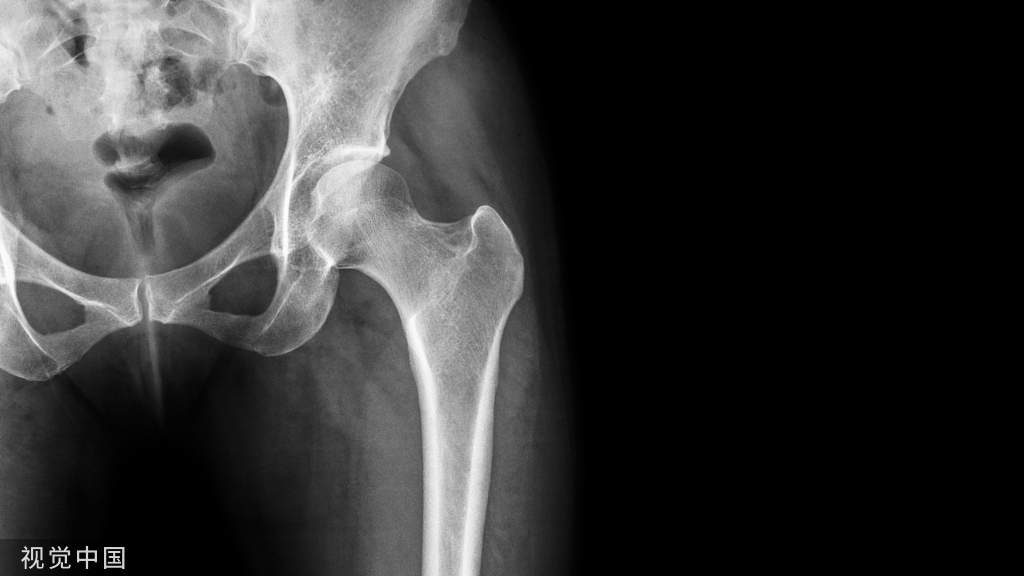

② 髋关节

病例4股骨颈骨折,在CT横断面骨窗上未见明显液体分层(a),在软组织窗(b)可见高密度血肿影(箭头所示,CT值为50HU)。

病例5股骨颈骨折,在CT横断面软组织窗上可见在髂腰肌内出现积脂血症表现。

病例6 一例82岁髋部外伤患者,非移位股骨颈骨折,在CT横断面可见积脂血症,MR证实股骨颈骨折。关节积脂血症在非移位股骨颈骨折的识别中作用明显。